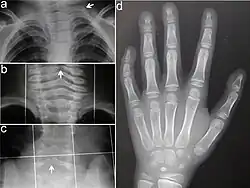

- nieprawidłowości budowy kośćca (100%)

- nieprawidłowe żebra lub kręgi (83%)

- opóźniony wiek kostny (79%)

- skrócenie kości długich dłoni (78%)

- brachydaktylia, klinodaktylia 5. palca (62%)

- nieprawidłowa krzywizna kręgosłupa (58%)

- skrócenie szyjki kości udowej lub dysplazja stawu biodrowego (50%)

- nieprawidłowości budowy mostka (29%)

- kostki wstawne (19%)